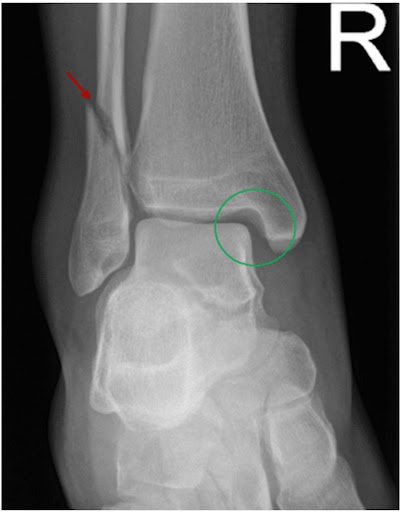

Ottawa Rules : untuk menentukan apakah diperlukan pemeriksaan penunjang X-ray pada pergelangan kaki. Ottawa Rules Positif apabila terdapat nyeri tekan disekitar mata kaki dan ketidakmampuan atlet atau pasien untuk melangkah / menapak 4 langkah. Apabila adanya kecurigaan ketidakstabilan sendi pergelangan kaki kronis, maka diperlukan pemeriksaan MRI untuk melihat derajat cedera ankle sprain dengan lebih akurat.